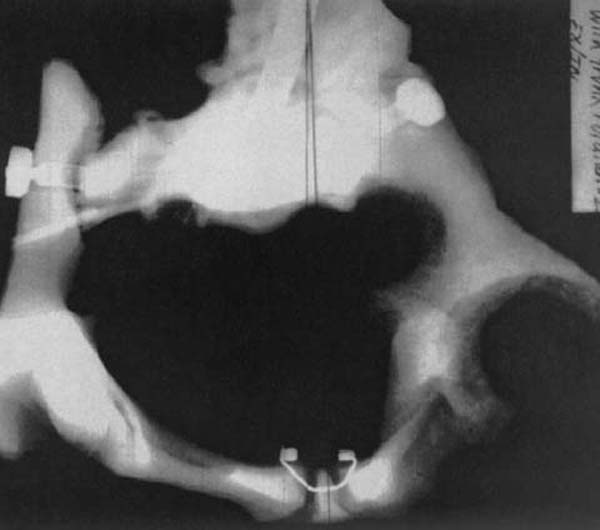

In addition, the innominates can rotate around a second axis either externally or internally. [74–76] Internal and external rotation of the ilia with respect to the sacrum is characterized by the changed position of the posterosuperior iliac spine either toward or away from the midline.

Note the lack of symmetry and distortion of the roundness of the pelvic bowl. Observe also the differences in space from the centerline through the pubic symphysis to each lateral aspect of the pelvic bowl. Figure 3 is an S to I radiographic view of a model demonstrating pelvic perimetry when the ilia have rotated externally and internally, as previously described.

| Figure 3.

Ex/In subluxated female pelvic bowl.

(Model) S to I view. Note lack of

symmetry, and distortion of

roundness of the opening.

Also note difference in space

from centerline through

pubic symphysis to right ilium.

(Radiograph provided courtesy of

Cherie Goble, DC.)

Again, notice the lack of symmetry and distortion of the roundness of the opening. Contrast the difference in space from the centerline through the pubic symphysis to the right ilium as opposed to the left ilium.